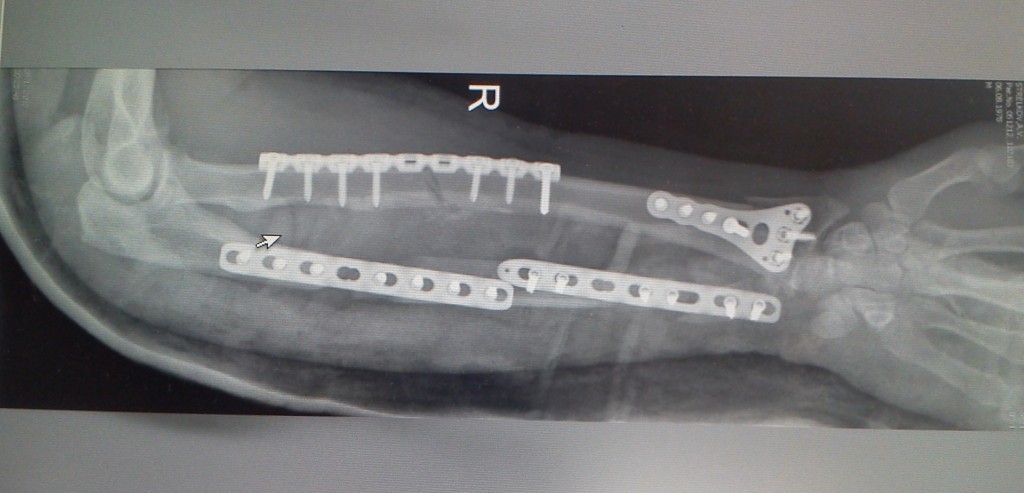

Перелом локтевой кости тяжелой степени предполагает оперативное лечение, методика которого будет зависеть от характера травмы. Многооскольчатый перелом и перелом локтевой кости со смещением лечится путем скрепления осколков посредством металлических пластин, штифтов или винтов, проволоки или нити. Рану ушивают, наносят на неё стерильную повязку и фиксируют руку в согнутом положении гипсом. При отсутствии патологии, препятствующей срастанию кости (сахарный диабет и пр.) гипс следует носить не менее трех месяцев. Обязательно назначается комплекс лечебных упражнений, которые позволяют восстановить двигательную способность руки.

Первым этапом врачебного вмешательства является незамедлительная операция, иначе есть риск не восстановить функцию конечности. Метод операции определяется в зависимости от локализации травмы и возраста пациента. Лечение может включать в себя резекцию проксимального фрагмента, чрескостный шов проволочной петлей, остеосинтез пластиной, спицами или спонгиозным винтом. После такой операции примерно на 3 недели накладывается гипс. Спустя неделю после оперативного вмешательства пациенту назначают лечебную гимнастику. В течение этой процедуры гипс временно снимают.